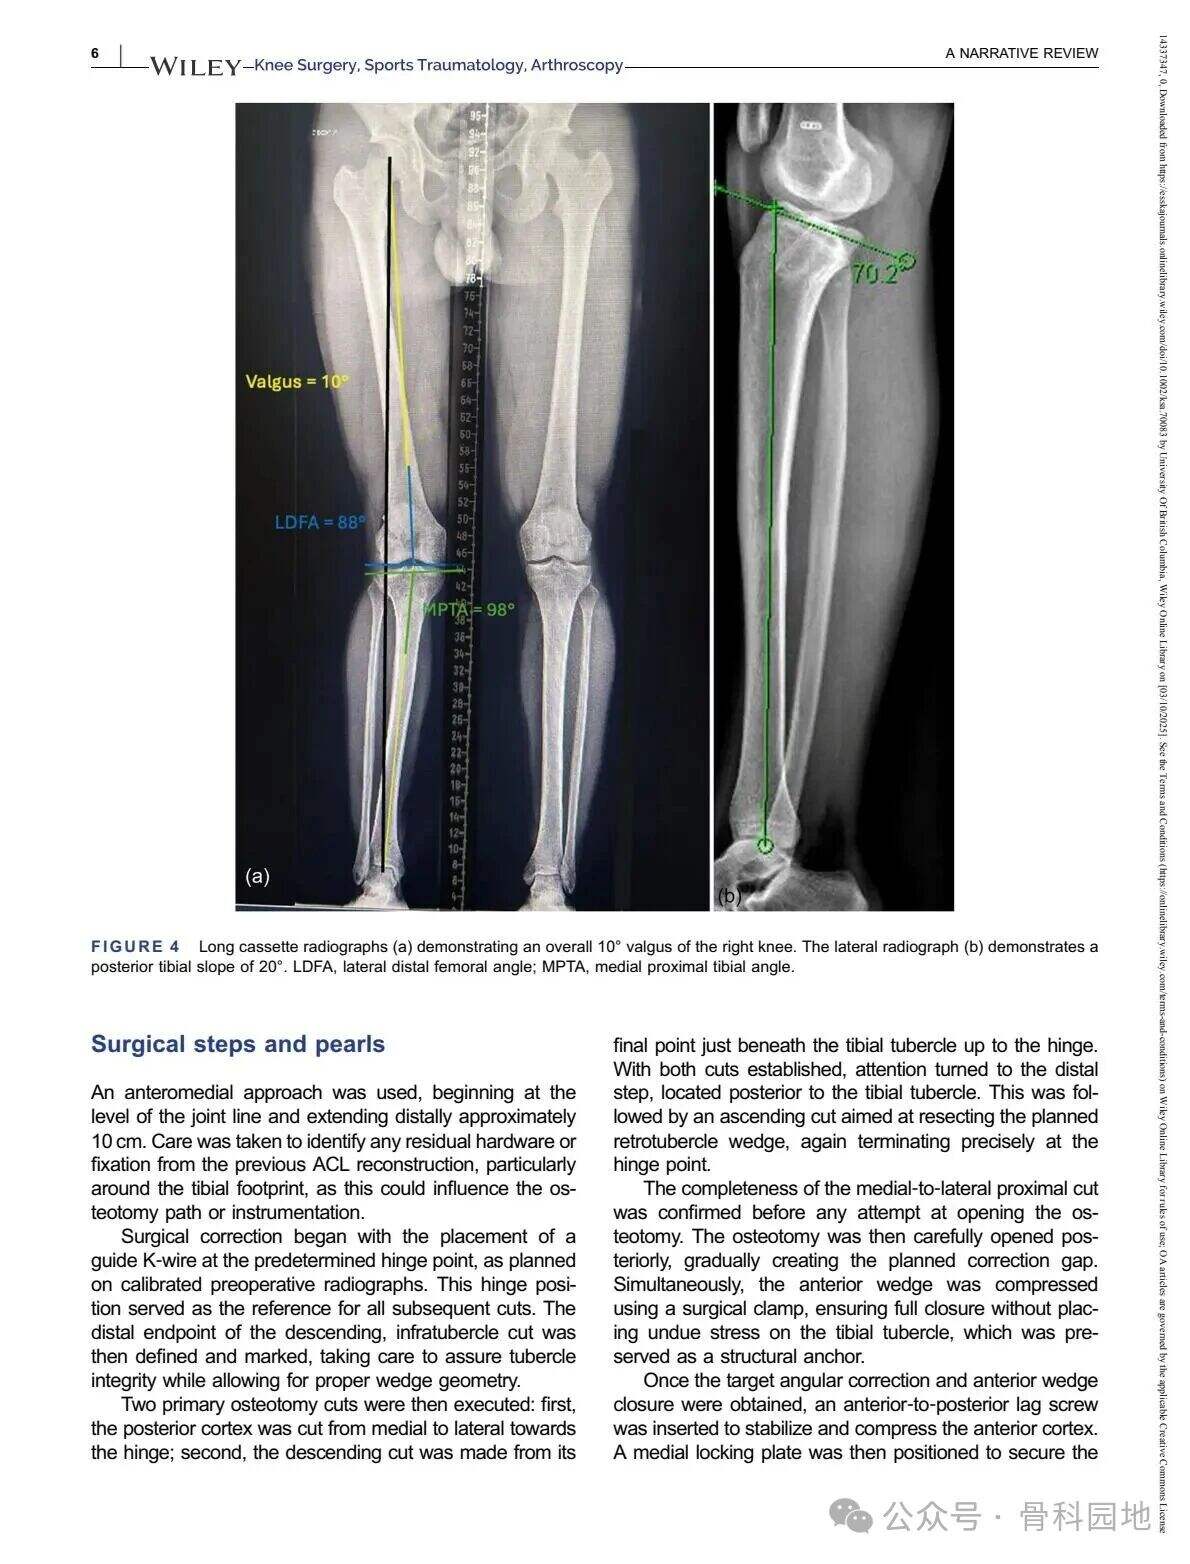

Čeprav konvencionalna visoka tibialna osteotomija (HTO) predvsem obravnava nepravilno poravnavo v koronalni ravnini, pomembnost poravnave v sagitalni ravnini – zlasti posteriornega tibialnega naklona (PTS) – ni mogoče prezreti v primeru nesposobnosti križnih vezi. Kombinirane nepravilnosti v koronalni in sagitalni ravnini so razmeroma redke in predstavljajo posebne kirurške izzive. Ta narrativni pregled povzema ustrezno literaturo ter predstavlja tehnične strategije za obravnavo zapletenih dvoravninskih nepravilnosti s pomočjo primerov iz prakse in razprav o različnih tehnikah.